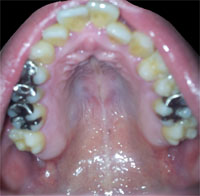

栃木県 24歳 男性

顔の歪みと噛み合わせが悪く、治療が可能なのか判断して頂ければと思います…。

以前、他のクリニックで診て頂いた事がありましたが、右の奥歯の位置が通常よりも1p程?(3年ほど前なので定かではありませんが)ズレているため、難しいとの事でした。

確かに、だいぶずれていらっしゃるようにお見受けします。